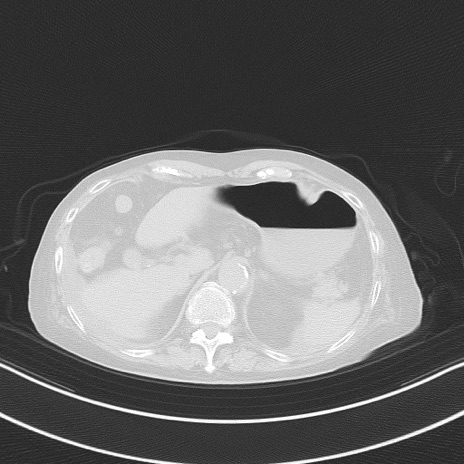

症例40(横断像)他院1日前

横断像